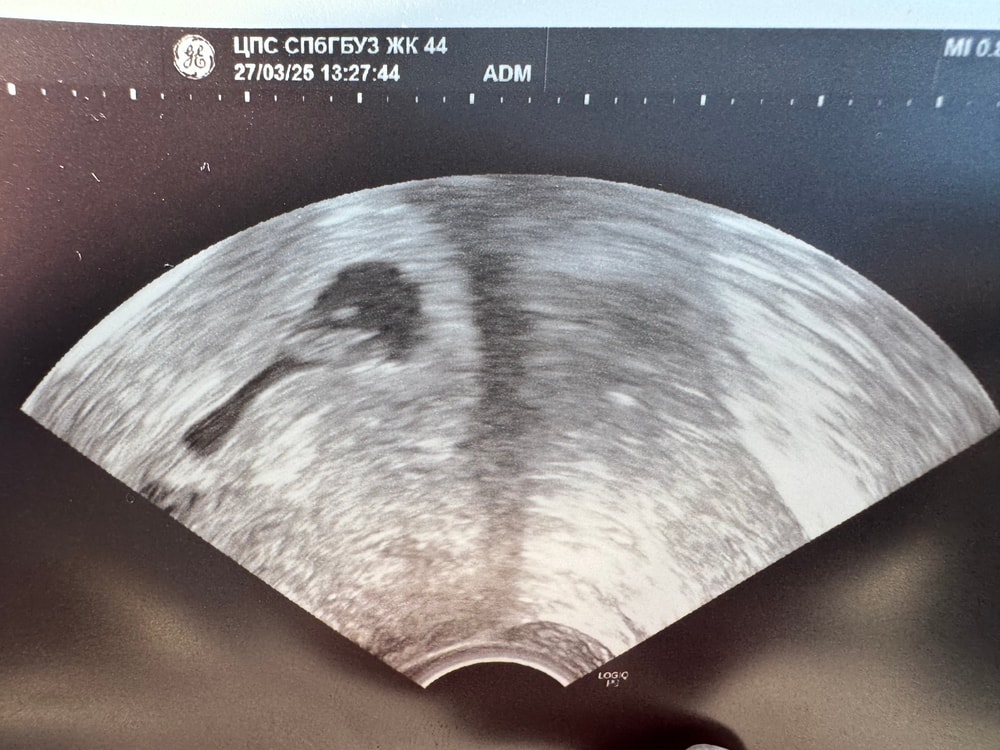

Первое узи прошли )21 дпп, все хорошо